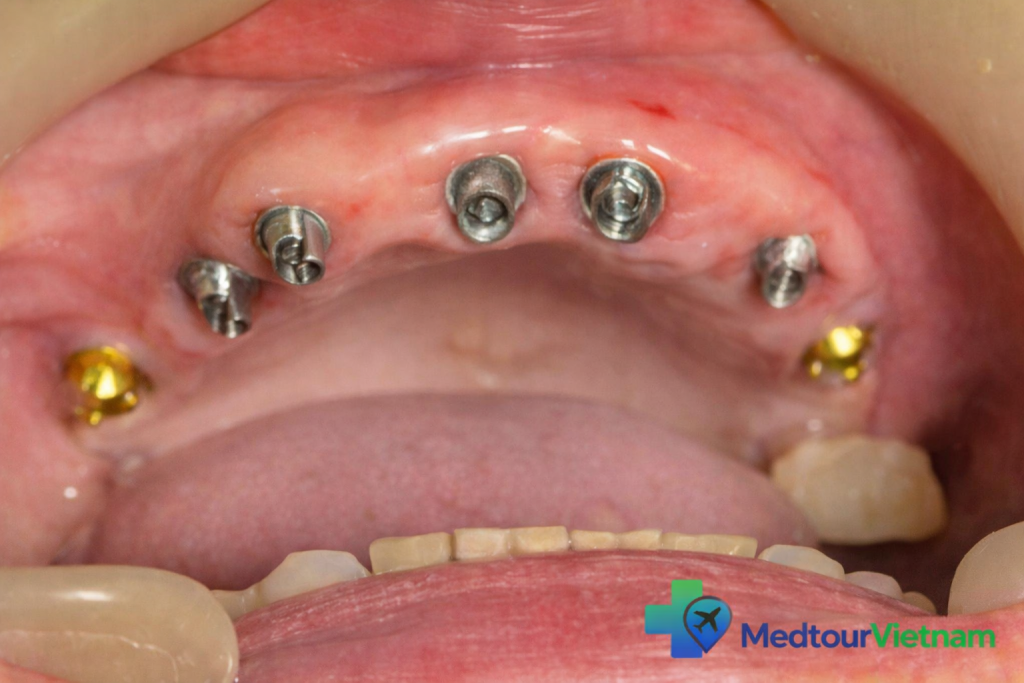

Placement of dental implant posts in the upper jaw during full mouth restoration

Step 3: Healing and Osseointegration (3–6 months)

Allow time for the implant to integrate with the bone

Can be done back home or during an extended stay in Vietnam